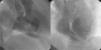

Coronary angiography showed no coronary lesions or signs of partially dissolved thrombus, and coronary flow velocity was normal (Figure 2). The septal branches from the left anterior descending and posterior descending arteries were reviewed carefully, but missing branches, significant atherosclerotic plaques or signs of ostial occlusion were ruled out. Ventriculography, performed to assess wall motion abnormalities, showed a VSD (Figure 3A and B and Online Video 1). Intravascular ultrasound was not performed given the progressive worsening in the patient's clinical situation and evidence of septal rupture after ventriculography. She was transferred to the coronary care unit for clinical stabilization before surgical repair. Transthoracic echocardiography (TTE) confirmed the presence of a 7 mm dissection involving the apical third of the septum (Figure 4A and B). Initially, a direct through-and-through defect resembling a simple rupture was observed (Online Video 2). However, additional images suggested a possible complex rupture with dissection tracts opening to the right ventricle in its mid segment (Online Videos 3 and 4). Initial measurements of cardiac troponin I and creatine kinase were 6.3 ng/ml and 267 IU/l, respectively, slowly decreasing in subsequent analyses. The patient's clinical condition progressively worsened, requiring inotropic support and intra-aortic balloon counterpulsation before emergency surgical patch repair.